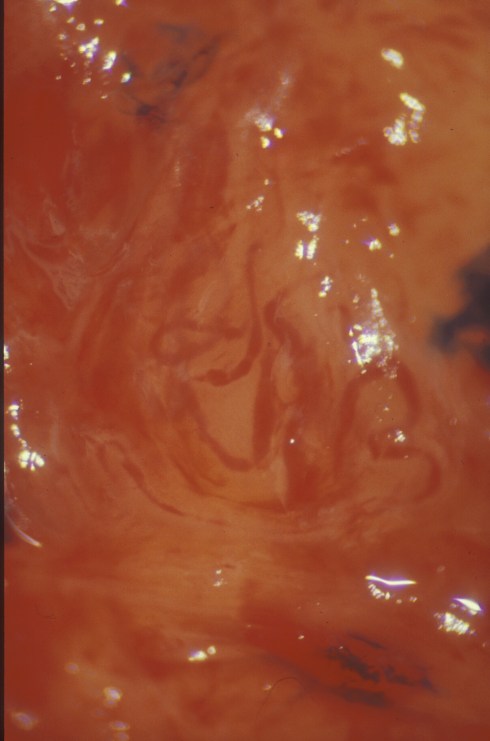

The last question was suggested to me in a preliminary, unpublished study of spiral arteries in decidual membrane that I did again with Yasser Daoud. The study attempted to improve our ability to sample acute atherosis in the fetal membranes. The entire membranes after removal from the placental margins were stretched over white cardboard cards, and a dissecting microscope was used to reveal the irregular spiral arteries. We sampled the visible spiral arteries for histological examination and made note of dilated segments that were suspected of being acute atherosis (35).

Fig 35: This is a membrane laid flat demonstrating a spiral artery with focal dilatation and hemorrhage.